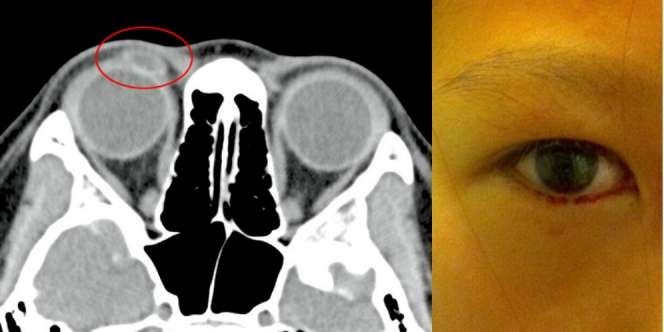

Bacalah kisah bocah perempuan berusia 11 tahun di Hong Kong ini. Matanya bengkak dan mengeluarkan darah karena matanya kemasukan lensa kontak selama dua tahun tanpa diketahui.

Kisah itu diketahui saat mata bocah itu bengkak dan mengalami peradangan selama dua minggu. Dokter mengira bocah ini mengalami bintitan, sehingga memberi anak itu antibiotik.

Namun bengkak itu tak kunjung kempis. Benjolan di mata kanan atas itu malah semakin parah. Dan bocah itu kembali dibawa ke rumah sakit untuk diperiksa kembali.

“ Anak itu menemukan darah di air matanya,” tulis Dr Sek Keung Kwok dan Dr Tommy Chung Yan Chan dalam laporan medis, sebagaimana dikutip Dream dari Asia One, Jumat 29 April 2016.

Pemeriksaan pun dilakukan. Bocah itu menjalani CT scan. Dan terlihat sebuah bayangan. Dokter mengira benjolan itu berisi kista. Untuk memastikan, dokter di klinik mata itu membua kelopak mata anak tersebut.

Dan betapa terkejutnya dokter itu. Saat membalik kelopak mata itu, sebuah benda bening terlontar ke luar. Setelah dicek, benda itu ternyata lensa kontak.

Setelah menemukan lensa kontak itu, ibu bocah tersebut teringat pernah kehilangan lensa kontak dua tahun silam. Sehingga mereka yakin lensa yang hilang itu adalah yang berada di mata anak itu.

Mereka menyimpulkan, lensa kontak itu telah mendekam di mata kanan bocah itu selama dua tahun. Sejak raib.

Dalam laporannya, para dokter menyorot pentingnya menjaga benda-benda sensitif dari anak-anak. Meski demikian, dalam laporan itu tak dijelaskan apa yang terjadi pada penglihatan bocah ini akibat lensa kontak itu.